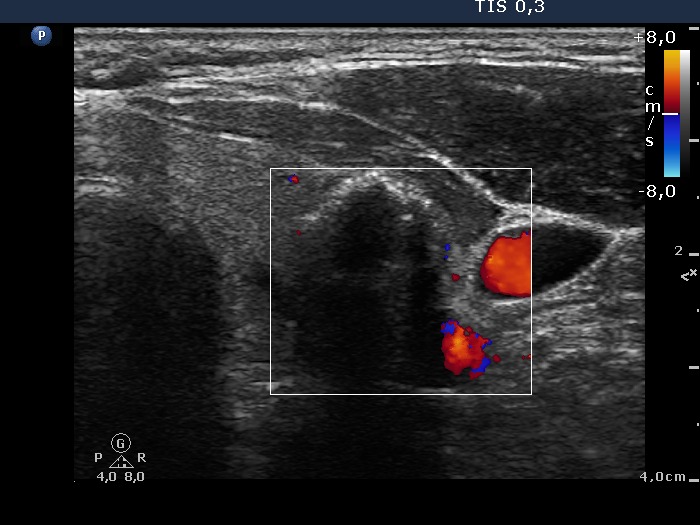

The borders of the nodule - case 186 (ultrasonographic picture 6)

Left lobe, transverse scan, color Doppler mode. The nodule displays neither perinodular nor intranodular blood flow.